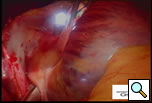

Video 1

The left chest is then prepped and draped and similar incisions are made, although slightly more posterior (Left Side MiniMAZE). The pericardium is opened posterior to the phrenic nerve, and pericardial stay sutures are placed. After similar mapping of ganglion plexi and PV ECGs, the ligament of Marshall between the left pulmonary artery and the left superior pulmonary vein is divided using cautery (Figure 5 and Video 2). Through a separate port site, the special lighted articulating dissector is placed under the left inferior pulmonary vein and articulated to emerge above the left superior pulmonary vein. The red rubber catheter attached to the dissector is again withdrawn behind the veins. The bipolar radiofrequency clamp is then brought around the left pulmonary veins using the rubber catheter as a guide. The clamp is again positioned on the atrial cuff (Figure 6) and isolation lines are created. Once isolation is complete, PV ECGs are obtained and pacing and high frequency stimulation are repeated to confirm bidirectional block before withdrawing the clamp. Next an Ethicon EZ 45mm thick tissue stapler (green load) (Ethicon Endosurgery, Cincinnati, OH) is introduced through the port. The anvil of the stapler is placed against the left atrium and the left atrial appendage is gently positioned in the jaws (Figure 7). The tip of the stapler usually rests under the left pulmonary artery to include the entire atrial appendage. The stapler is then fired, and the left atrial appendage removed. Bipolar cautery is used to control occasional oozing from the cut atrial edges. A bipolar ventricular pacing wire is then secured inside the pericardium overlying the left ventricle and the pericardium is closed with interrupted sutures. The pacing wire and chest tube are brought out through the port site and the incisions are closed.